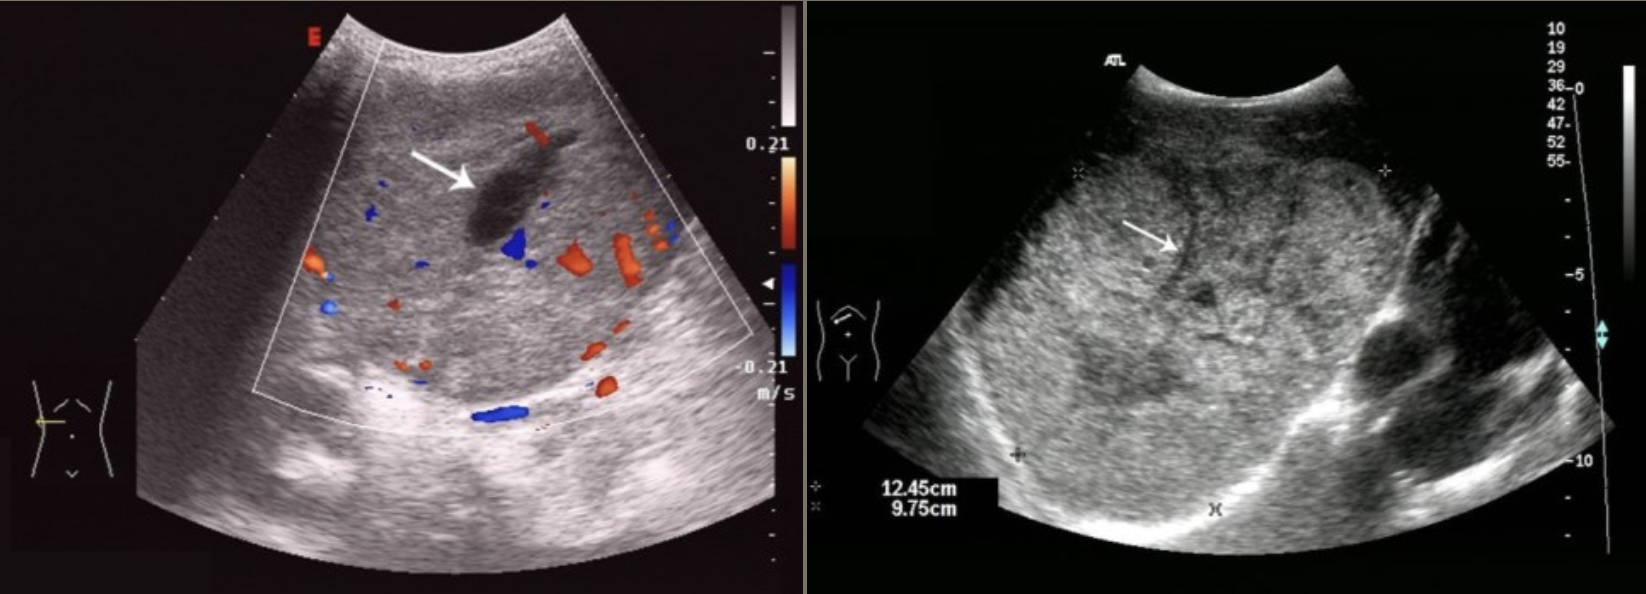

FNH (Focal Nodular Hyperplasia) → common, benign liver mass

2D US: well-defined, ~5 cm, usually solitary, central hypoechoic scar, isoechoic to hypoechoic to liver

color doppler: central scar → stellate scar doppler pattern (pinwheel)

DDX: hepatic adenoma, hemangioma, HCC